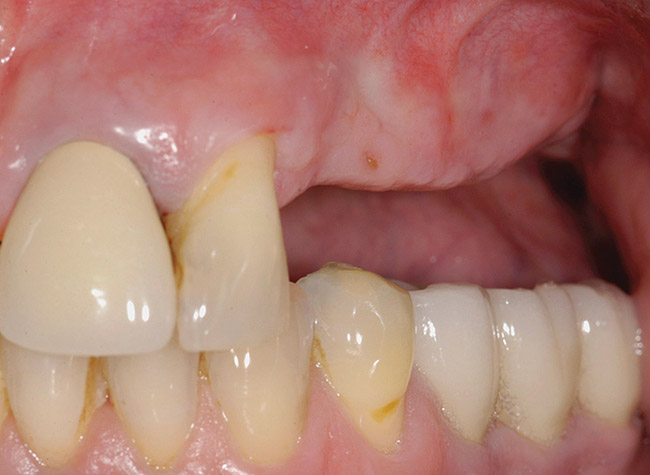

Figure 11  Edentulous left posterior maxilla with alveolar ridge deficiency.

Figure 11

A 62-year-old woman was referred for fixed tooth replacement of the missing maxillary left cuspid, bicuspids, and first molar (Figure 11). Clinical and CBCT evaluation revealed an almost fully pneumatized maxillary left sinus along with alveolar width deficiency. The treatment plan called for a four-unit, implant-supported splinted fixed bridge. A left sinus augmentation along with a ridge split and interpositional bone graft consisting of rhBMP-2/ACS (INFUSE Bone Graft) and mineralized allograft (MinerOss) covered by a dense porous polyethylene mesh (Medpor®, Stryker, www.stryker.com) were done simultaneously (Figure 12, Figure 13 and Figure 14). Six months later, a follow-up CBCT revealed a well-incorporated graft with adequate bone volume and density for implant placement (Figure 15 and Figure 16). Final bridge fabrication followed 3 months later (Figure 17 and Figure 18).